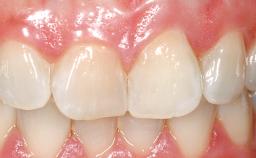

A 36-year-old female patient was referred for the replacement of the upper left central incisor (tooth 21), which had fractured. Although the tooth had been asymptomatic for many years, the crown began to loosen, at which time she presented to her dentist for an assessment. Teeth 21 and 22 had both been endodontically treated many years previously. She was a healthy individual and a non-smoker.

On examination, the patient had a low lip line and only displayed the coronal half of the anterior teeth when smiling.